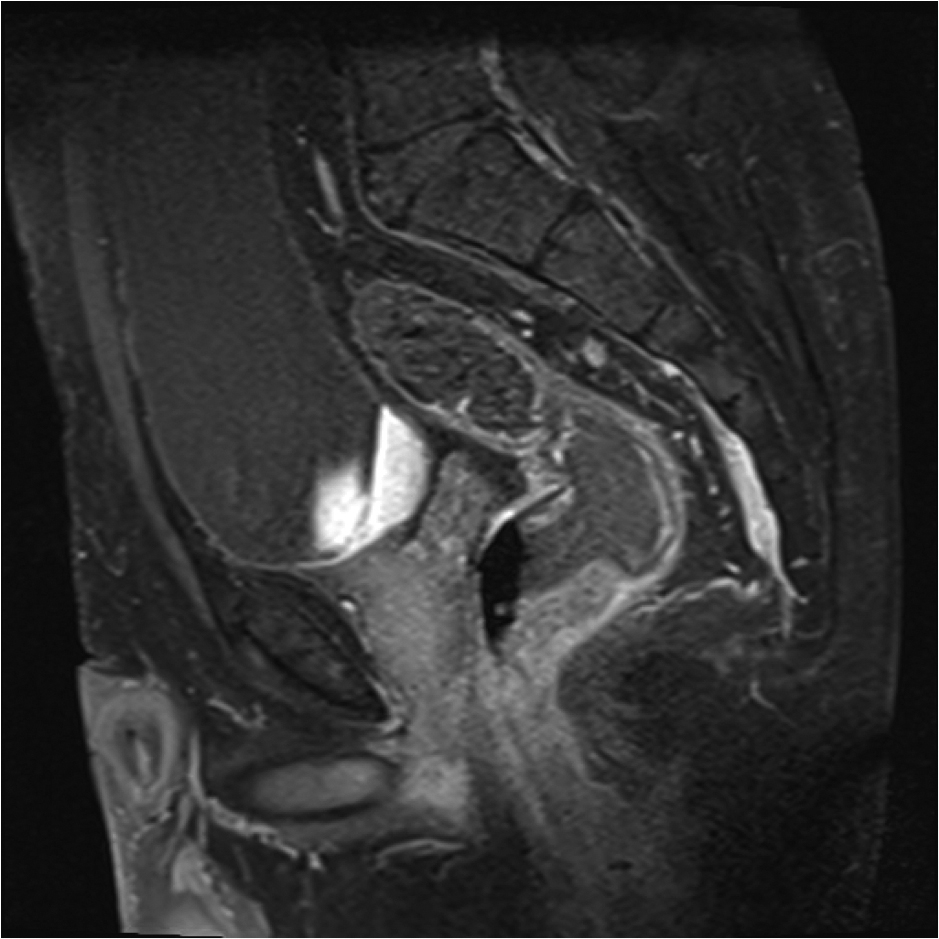

Fig.2. Același pacient post chimio-/ radioterapie – răspuns complet cu dispariția masei tumorale rectale; dispariția restricției de difuzie și reducere în dimensiuni a ganglionilor mezorectali; pacientul a beneficiat de TME şi s-a confirmat histopatologic absenţa ţesutului tumoral (pT0 pN0).

a-d) imagini T2 ponderate în 3 planuri

e) difuzie RM (b1000)

f) sagital T1 postcontrast